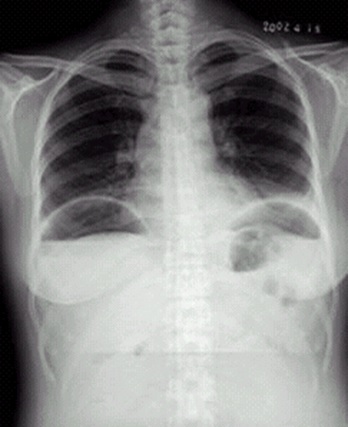

04卷-4.病史:女性,42歲,腹痛1天,進行性加重。診斷

A.腸梗阻

B.腸結(jié)核

C.正常腹平片

D.消化道穿孔

題目解析:【該題針對“ X線-消化道穿孔 ”知識點進行考核】